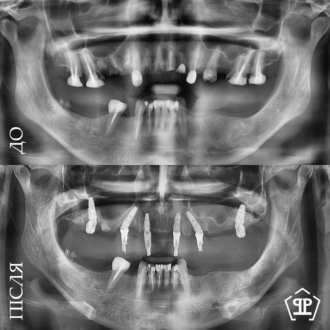

Клинический кейс комплексной реабилитации: проведена имплантация с последующим протезированием коронками, установлены коронки во фронтальном участке, виниры на нижние зубы и восстановлена ​​высота прикуса. В результате восстановлена ​​жевательная эффективность, стабилизированный прикус, равномерное распределение нагрузки и эстетическая улыбка.

Показательный кейс одноэтапной имплантации All-on-6 на верхней челюсти. Импланты установлены в кости под углом, минуя гайморовые пазухи.

Выполнено тотальное протезирование на имплантатах по протоколу All-on-6 для обеих челюстей. На верхней челюсти установлена циркониевая керамическая конструкция на фрезерованной титановой балке, обеспечивающая высокую прочность и эстетику. На нижней челюсти изготовлена металлокерамическая ортопедическая конструкция на 6 имплантах. Произведено поднятие высоты прикуса, что позволило восстановить правильную окклюзию и гармонизировать профиль лица. Установлены несъемные конструкции, обеспечивающие полноценное функциональное и эстетическое обновление.